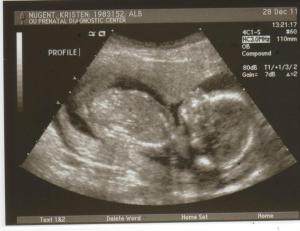

Posted in Uncategorized A Baby Girl Posted on December 29, 2011 by kokomeau Baby girl Today I learned I am going to have a granddaughter. I feel overwhelmed with surprising emotion. I cannot wait to meet her. May of next year. Did I say I cannot wait to meet her? Share this: Share on X (Opens in new window) X Share on Facebook (Opens in new window) Facebook Like Loading... Author: kokomeau View All Posts